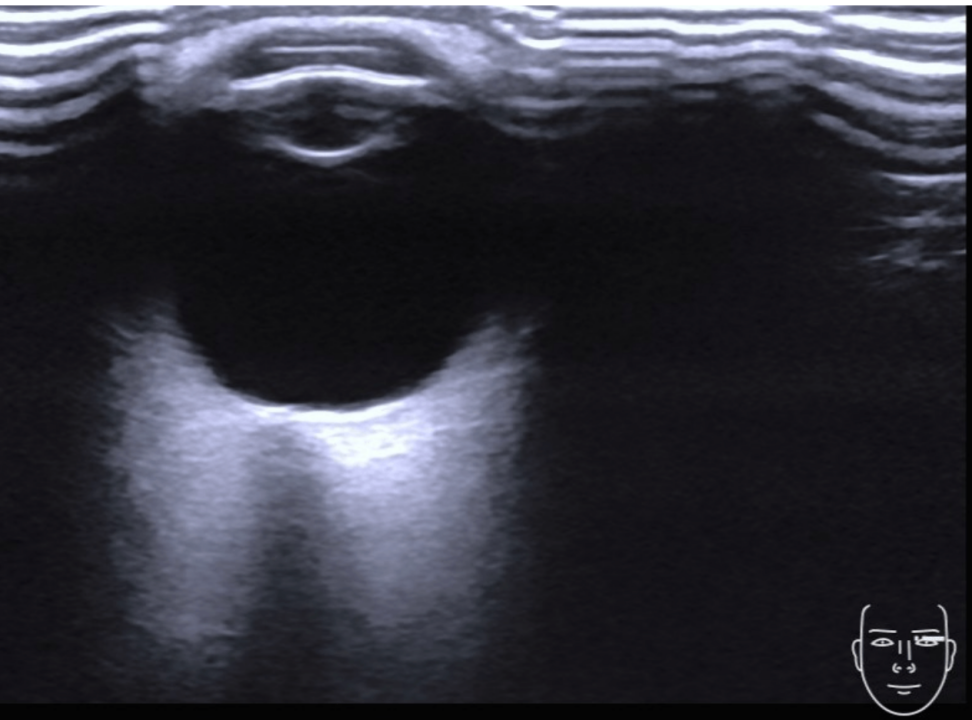

四、检查手法:将探头水平至于闭合的眼睑上,涂抹足量耦合剂,轻压眼球,探头方向朝正下方或略向内侧偏斜,检测深度为40-50mm,获得眼窗

方法:将多普勒取样框置于眼球后15~25mm处,在视神经的两侧寻找类似英文字母“S”的粗大血管,即眼动脉。